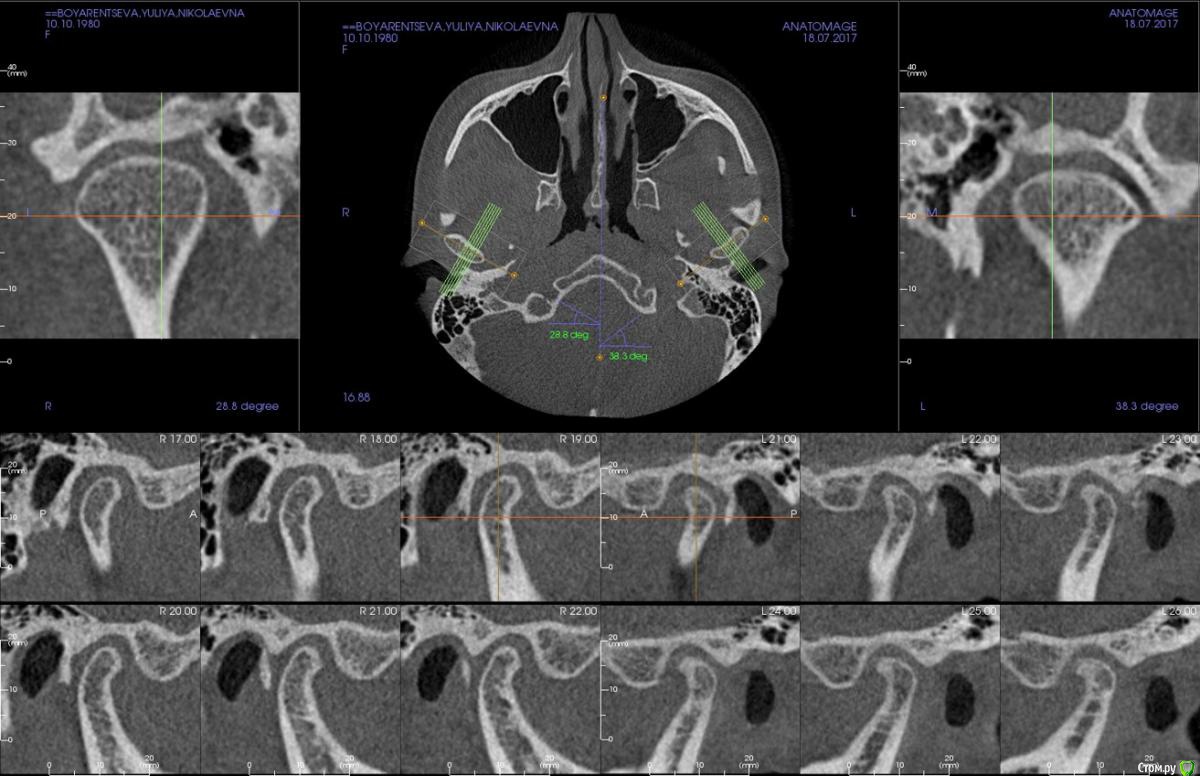

kapyulia Опубликовано 22 декабря, 2017 Поделиться Опубликовано 22 декабря, 2017 Добрый день! Могли бы Вы подсказать есть ли необходимость в удалении зубов (пятерки) с верхней челюсти? Спасибо за помощь. Ссылка на комментарий